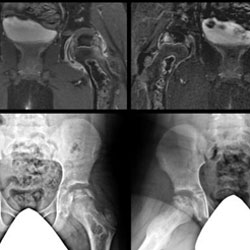

Management of pediatric femoral head osteonecrosis (FHO) due to various etiologies remains a clinical challenge due to delayed diagnosis, limited evidence to guide treatment decision making, and a lack of consensus on treatments to prevent the femoral head deformity.  Since many review articles have been written on Legg-Calve-Perthes disease, this review focuses on pediatric FHO secondary to trauma, sickle cell disease, and corticosteroid therapy. Post-Traumatic FHO is a serious complication that can occur following femoral neck fractures and traumatic hip dislocations in children. Sickle cell disease is the most common inherited blood disorder in the US and is a common cause of multi-focal osteonecrosis in patients of African descent and from the sub-Saharan Africa, the Mediterranean, the Persian Gulf, and the Indian subcontinent.  Corticosteroid induced osteonecrosis in patients with acute lymphocytic leukemia is of particular interest since acute lymphocytic leukemia is prevalent in the pediatric population.  The goal of this review is to educate the clinician on the epidemiology, pathophysiology, natural history, evaluation, and treatment considerations for pediatric FHO secondary to these conditions.